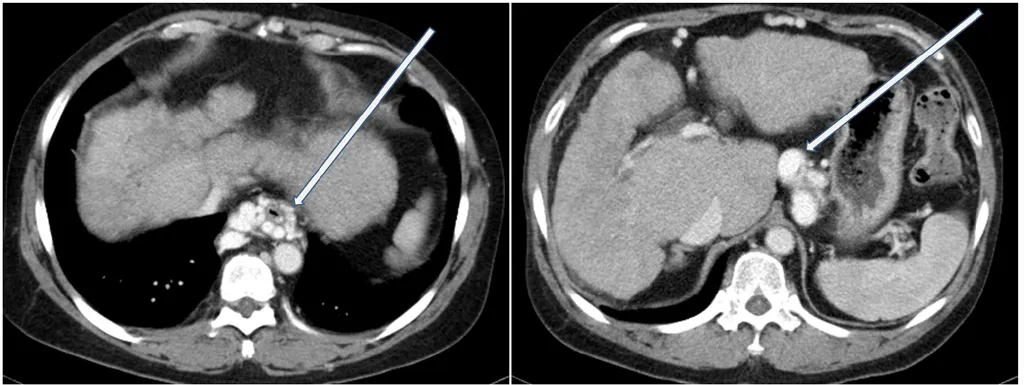

【109-2 醫學(三) 第75題】

一名酗酒男性因腹脹和食慾不佳來求診。超音波檢查發現病人有肝硬化,電腦斷層檢查呈現如圖,箭號所指之異常最可能是下列何種疾病所造成?

詳解

破題關鍵

這名有肝硬化的酗酒男性,其電腦斷層影像中箭號所指的異常是明顯擴張且彎曲的血管,這些是典型的食道或胃靜脈曲張,直接指向肝門靜脈高壓。

選項拆解